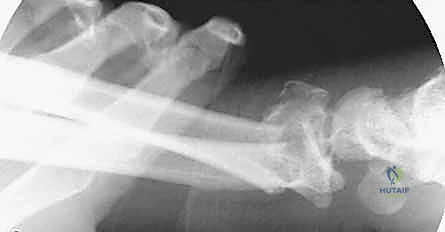

- الأشعة السينية (X-rays): بأوضاع متعددة لتقييم زوايا الكسر ومقدار الانهيار العظمي.

- الأشعة المقطعية (CT Scan) مع إعادة البناء ثلاثي الأبعاد (3D Reconstruction): وهي خطوة إلزامية في الكسور المعقدة. تتيح للدكتور هطيف رؤية كل شظية عظمية داخل المفصل بدقة متناهية والتخطيط للعملية الجراحية قبل دخول غرفة العمليات.

لفهم قيمة "الصفيحة الجسرية"، يجب أن نقارنها بالبدائل المتاحة. في حالات التفتت الشديد (حيث يكون العظم أشبه بالزجاج المهشم)، تفشل العديد من الطرق التقليدية.

مبدأ عمل الصفيحة الجسرية (Distraction Ligamentotaxis)

تعتمد هذه التقنية المتقدمة على مبدأ إبقاء المفصل مشدوداً ومثبتاً من الخارج. الصفيحة تعمل كـ "جسر" يعبر فوق منطقة الدمار الشامل في العظم، وترتكز على عظم سليم في الساعد وعظم سليم في اليد. هذا الجسر يمنع العظم المفتت من الانهيار ويسمح للشظايا الصغيرة بالالتئام في مكانها الصحيح بفضل الشد الطبيعي للأربطة المحيطة.